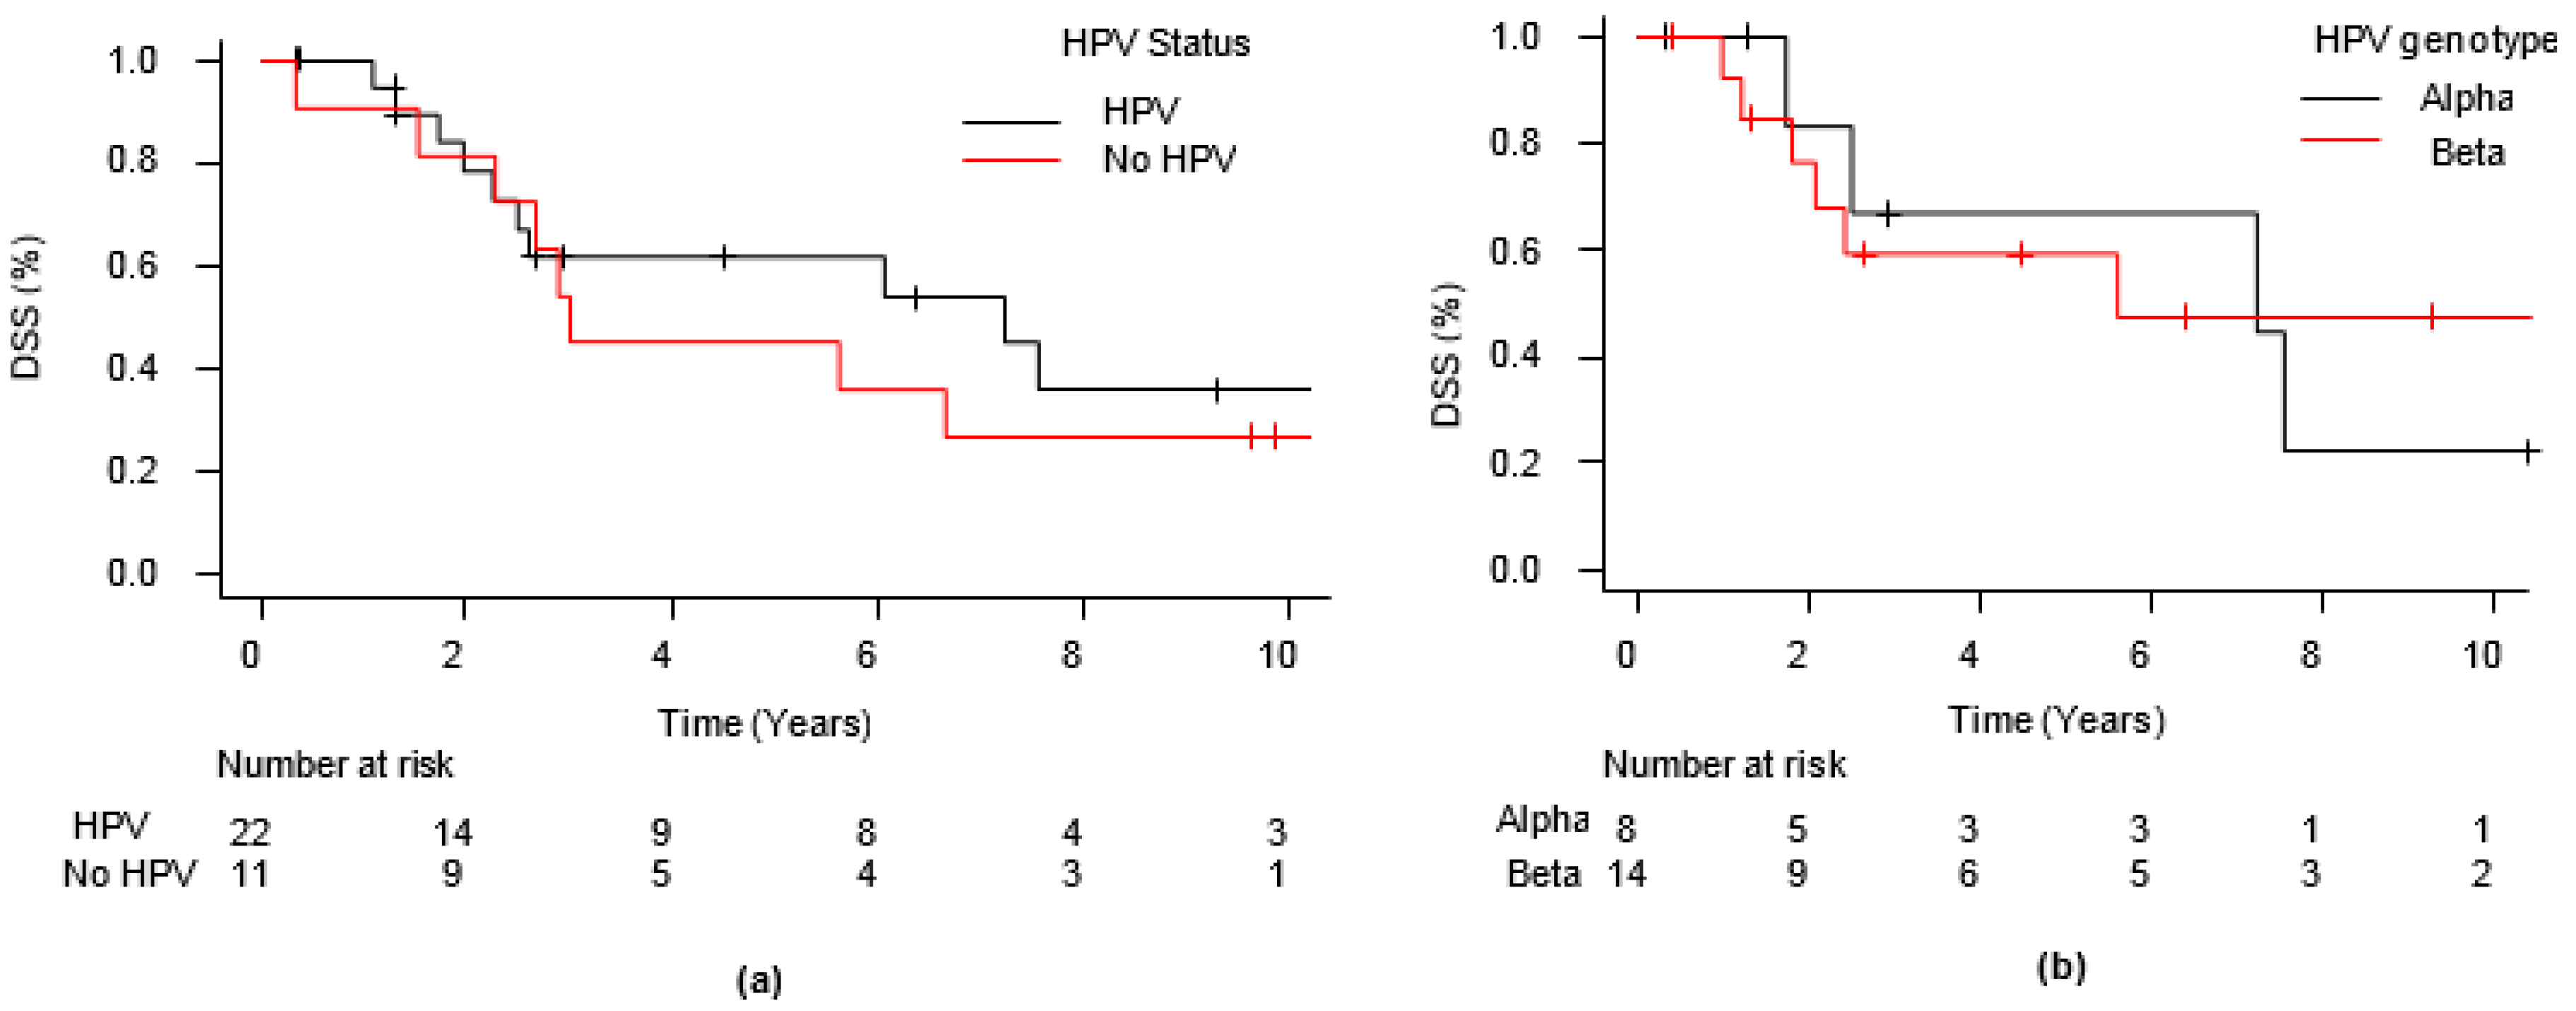

3. Results

| HPV positivity | 22 (66.7) |

| Alpha | 8 (36.4) |

| Beta | 14 (63.6) |